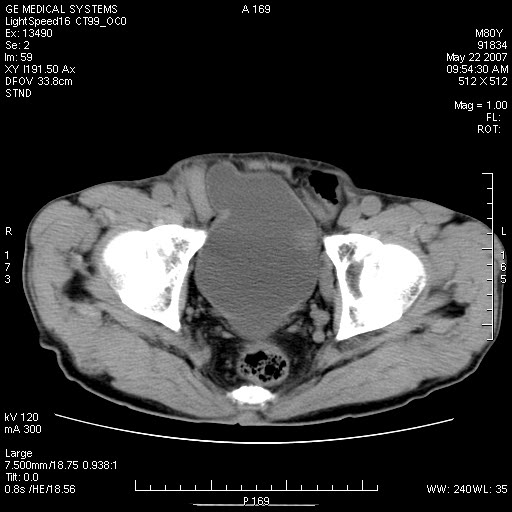

标题: CT8346:男,80岁。血尿,肝脏,膀胱占位,是否为肝转移?

男,80岁。血尿,无腹部不适病史。

膀胱病变:

肝脏内病灶有假包膜,增强扫描动脉期有动静脉瘘,有快进快出特点,考虑原发性肝癌。病灶内有裂隙样低密度影,以纤维板层样细胞癌可能性大。膀胱左侧乳头状占位,增强呈明显强化,左侧盆腔内有肿大淋巴结,结合有血尿病史,考虑膀胱癌左侧盆腔淋巴结转移。